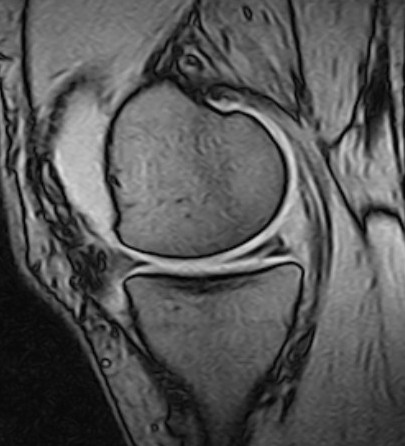

Traumatic meniscus injuries are most often seen in active younger individuals and are often high-energy injuries, not infrequently associated with damage to the anterior cruciate ligament (23). Typical traumatic tears are 'bucket handle'-shaped (longitudinal, vertical (Figure 2, Figure 3), and with the torn part of the meniscus potentially folded over towards the intercondylar eminence), radial, or flap-shaped. Folded bucket-handle tears can restrict both flexion and extension, and early repositioning and suturing are indicated to prevent shrinkage and destruction of the meniscus tissue.

Meniscal root tears are injuries at the site of or close to the posterior attachment of the menisci to the tibia (posterior root tears) (Figure 2) (24). Medial root tears are most often seen in degenerative knees as part of the development of osteoarthritis, and lateral root tears are most often seen in younger patients with damage to the anterior cruciate ligament. Root tears often cause more pain and effusion than other meniscus injuries.

Secondary MRI findings can include meniscal extrusion or associated bone marrow oedema (25). Extrusion occurs when the meniscus is either torn radially or close to the root (trauma) or stretched (degeneration) and thereby squeezed out of position in the joint. This leads to partial or complete loss of function of the meniscus – comparable to the effect of complete surgical resection (26). Meniscal extrusion is thought to increase the risk of rapidly progressive osteoarthritis (27).